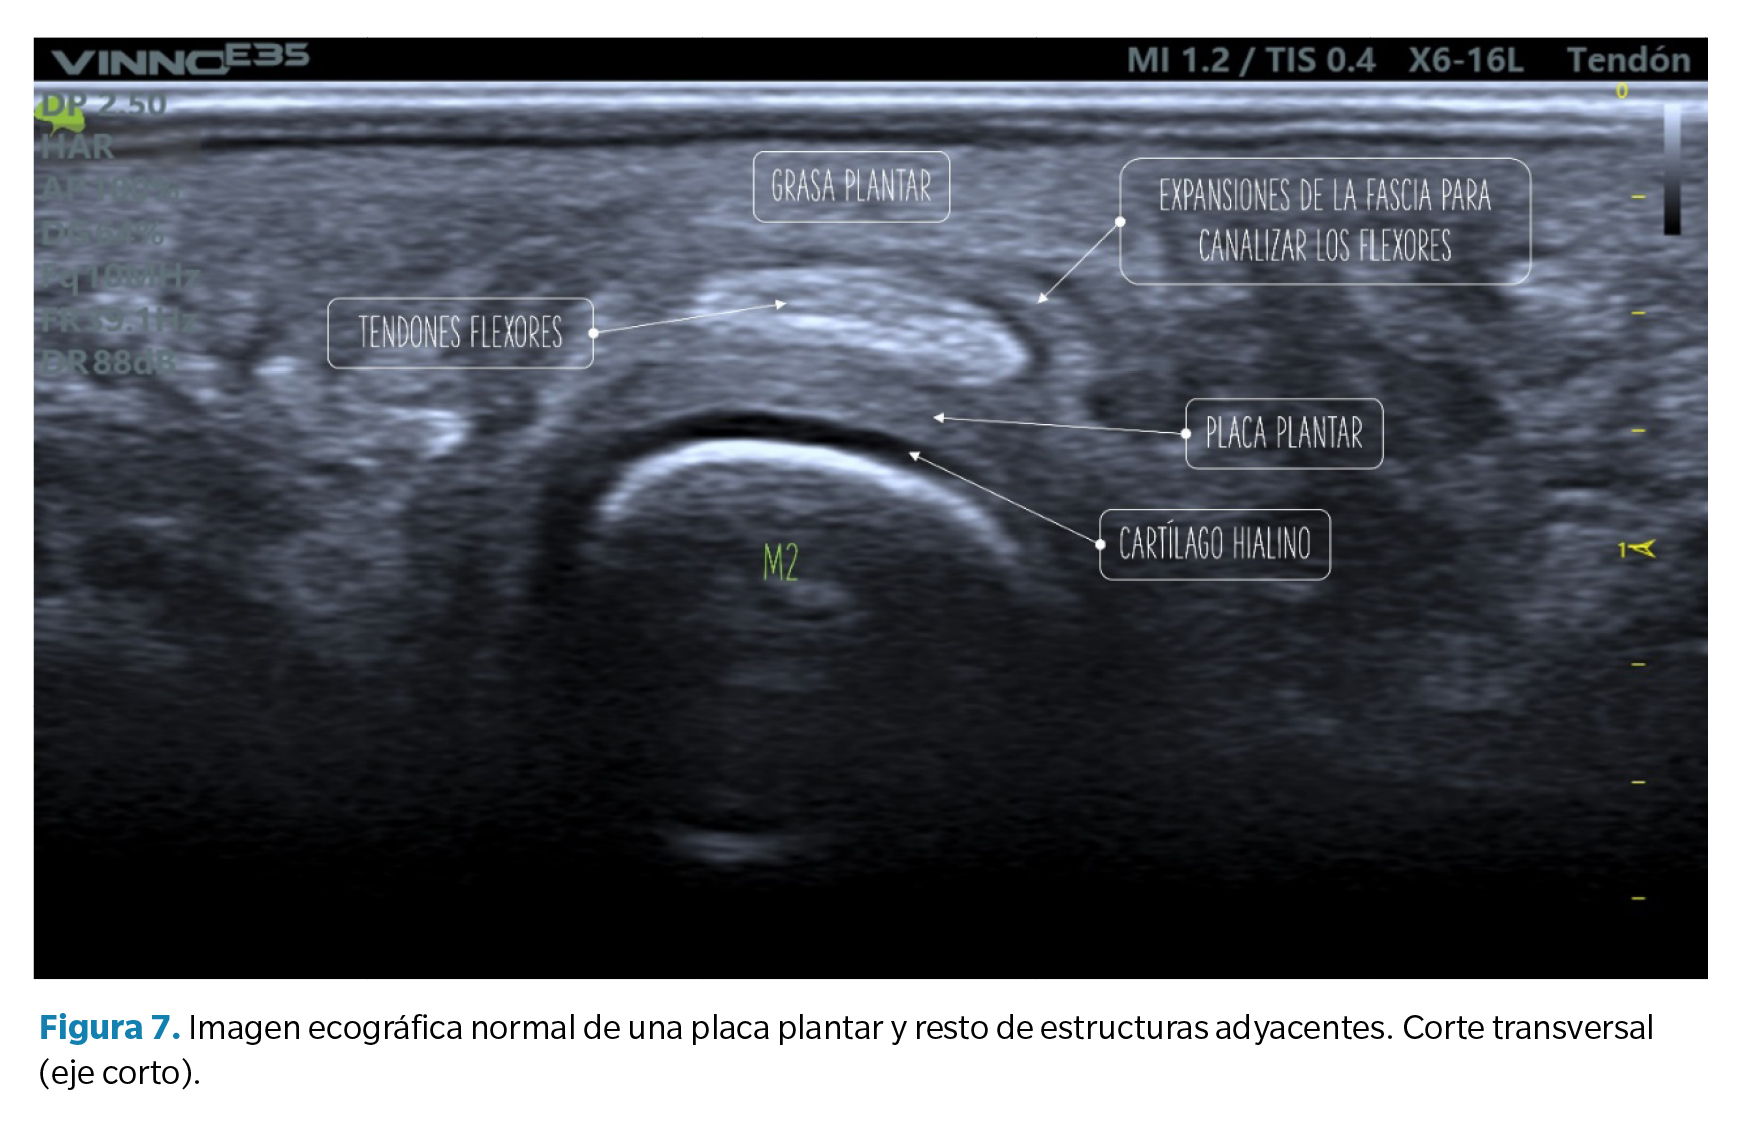

• Corte transverso (eje corto): la placa plantar tendrá una forma curvada que acuna a la cabeza metatarsal. La ecotrama es igualmente granulada, si bien en este corte el aspecto del moteado puede ser más heterogéneo al reflejar la disposición longitudinal de los haces de colágeno. Sobre la placa se revelan los tendones flexores que pueden identificarse fácilmente mediante maniobras de anisotropía (Figura 7).